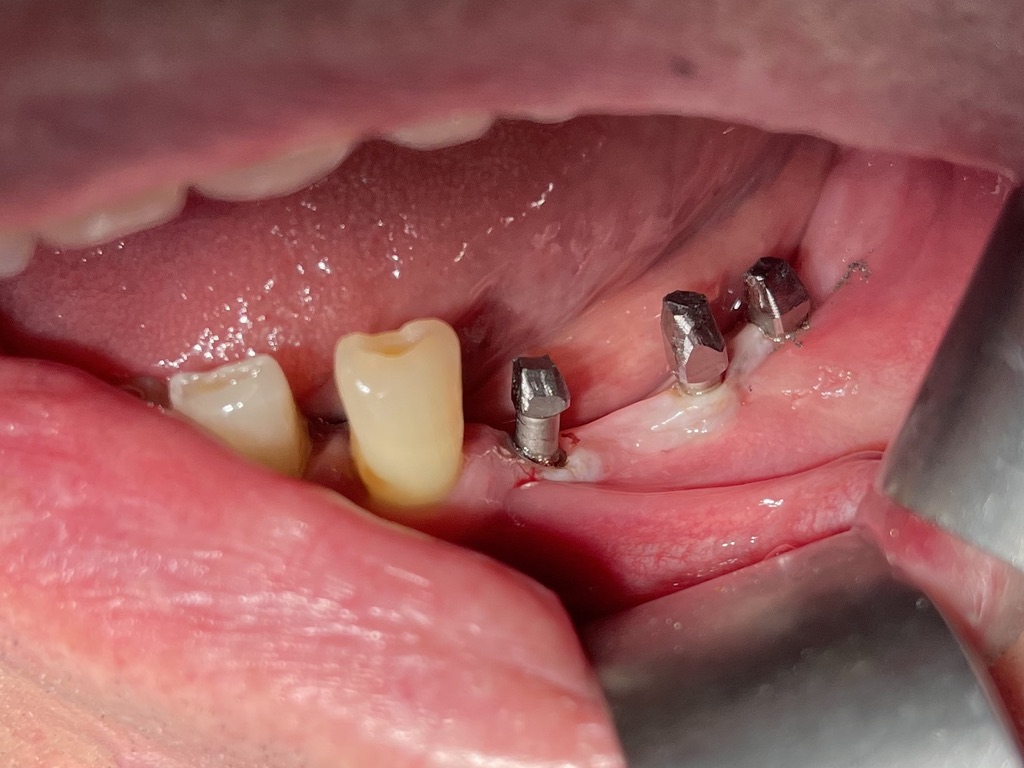

3 - FORMA DEGLI IMPIANTI E DENSITÀ DELL'OSSO

Ovvero: perchè l’impianto di Tramonte va così bene. 1° motivo: forma adeguata alla struttura.